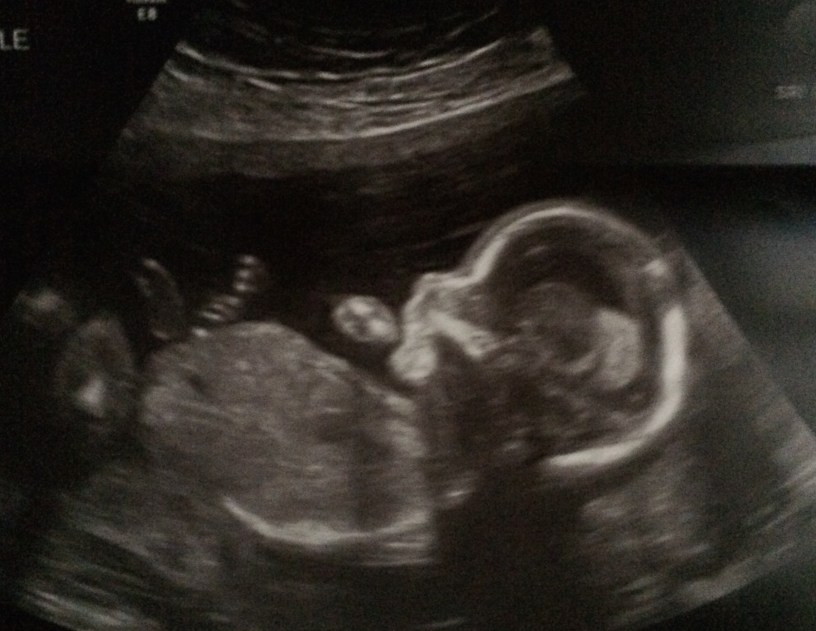

I’ve been meaning to write to you, but it has been difficult to find the words to say so I’ve continued to put it off. In my pain, it was easier not to think about you. As you have grown bigger and stronger, so have your kicks. What started as soft little sensations has turned into more insistent pokes, little reminders that I need to think about and connect with you.

Your life has such a great purpose. The very fact that you are here is a miracle. While your sister was born from months of planning and intention, you were born from a single moment of passion and faith. And a passionate, faith-filled man you will grow up to be. Just like your father.